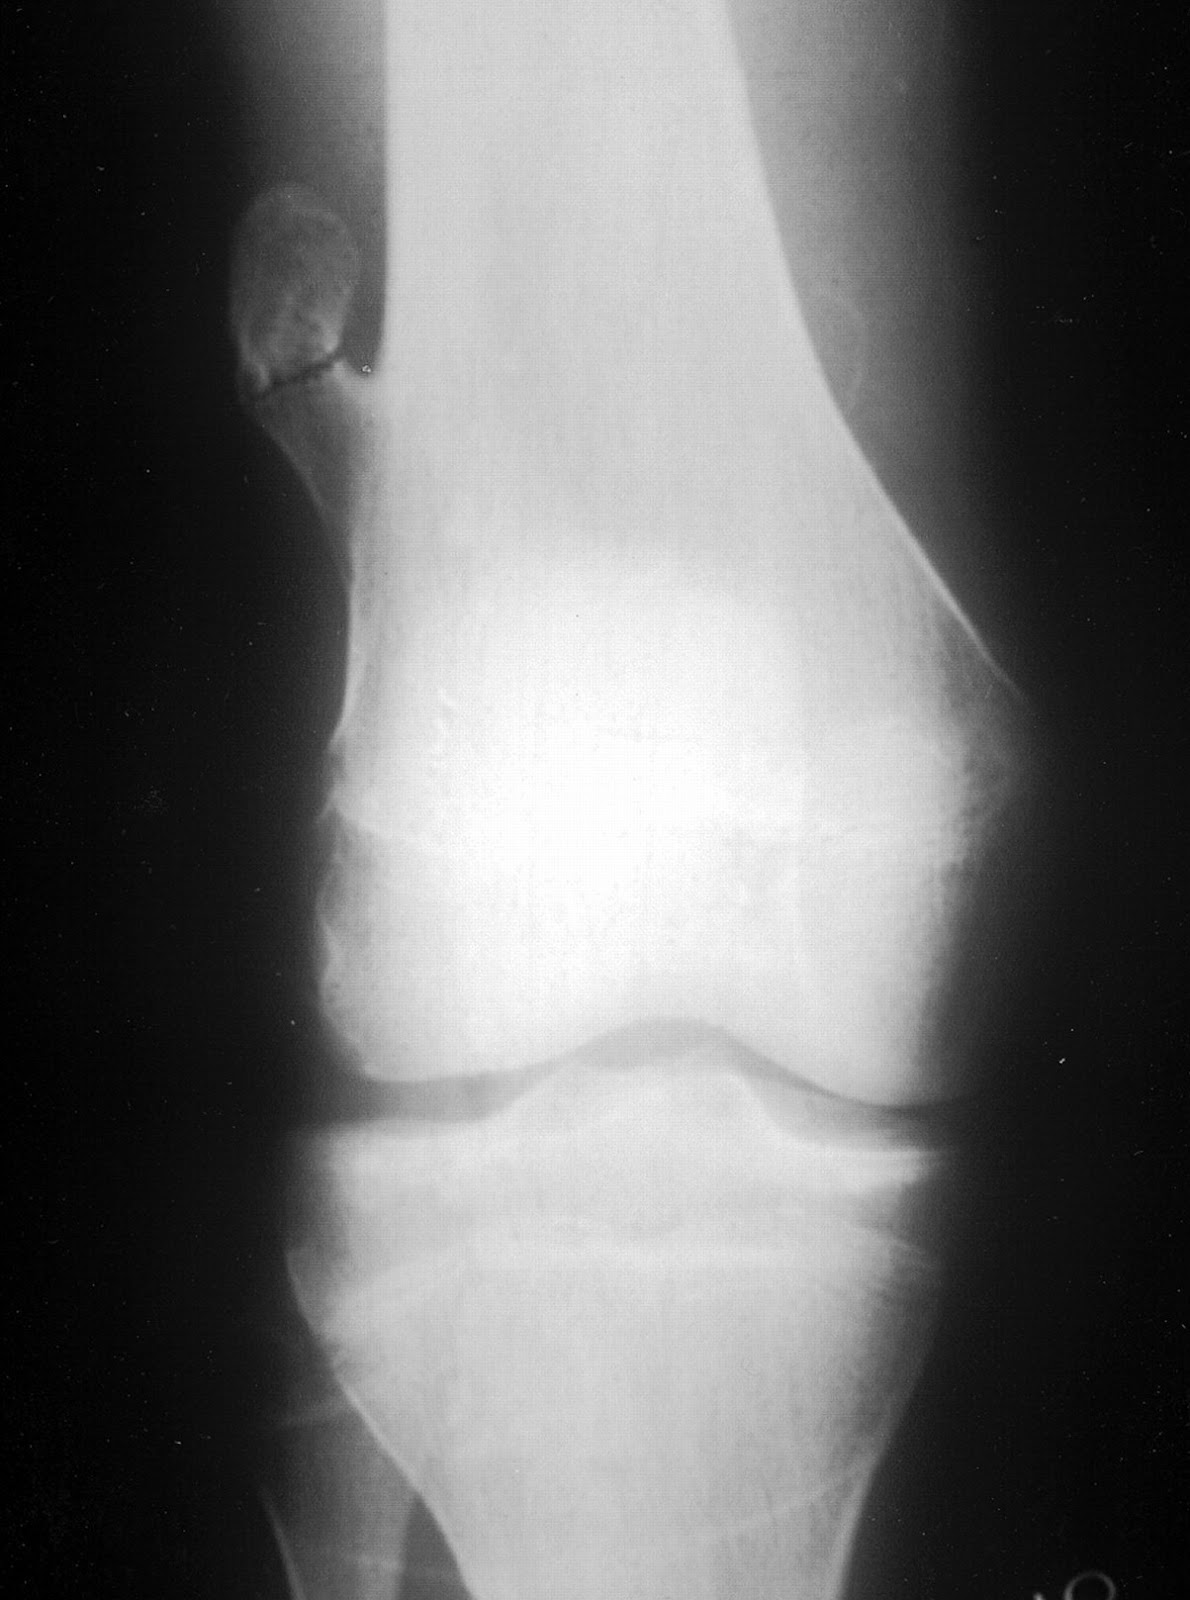

An 17 year old boy presenting with swelling in lower thigh which was progressively increasing in size, having pain since 10 days.

OSTEOCHONDROMA (EXOSTOSIS) Definition: - Cartilage capped bony projection arising on the external surface of bone containing a marrow cavity that is continuous with that of the underlying bone. Epidemiology: - Most common bone tumor. - Osteochondroma may be solitary or multiple, the latter occuring in the setting of hereditary multiple exostoses. - Solitary lesions account for 80% of cases, and most affected patients are diagnosed in their second decade of life - Male preponderance with a male to female ratio 1.5-2:1. - Hereditary multiple exostoses (HME) is an autosomal dominant genetic disorder , and has prevalence of 1 per 50 000 in the general population making it one of the more common inherited skeletal disease. - Patients with HME come to medical attention at the younger age , usually during first decade, because they cause severe skeletal deformities and are frequently polyostic. Sites of involvement: - Generally arise in bones performed by cartilage. - Most common site of involvement is the metaphyseal region of distal femur, uppr humerus, upper tibia and fibula. Clinical findings: - Many, if not most lesions, are asymptomatic and found incidentally. In symptomatic cases, the symptoms are often related to the size and location of the lesion. - Most common presentation is that of a hard of long- standing duration. Imaging: - Bulbous lesions on X rays, and they a narrow or broad (sessile) osseous radiosense stalk, which is attached to the underlying bone. - The characteristic feature is a projection of the cortex in continuity with the underlying bone. - Excessive cartilage type flocullent calcification should raise the suspicion of malignant transformation. - CT scan or MRI images typically show continuity of the marrow space into the lesion. A thick cartilagenous cap rises suspicion of malignant transformation.Gross: - May be sessile or pedunculated. - The cortex and medullary cavity extends into the lesion. - The cartilage cap is usually thin. - A thick an irregular cap (greater than 2 cm) may be indicative of malignant transformation. Histopathology: - Lesion has three layers - perichondrium (fibrous layer covering cartilage), cartilage and bone. - Outer layer is a fibrous perichondrium that is continuous with the periosteum of the underlying bone. - Below this is a cartilage cap that is usually less than 2 cm thick (and decreases with age). - Within the cartilage cap the superficial chondrocytes are clustered, whereas the ones close to bone resemble growth plate. - Loss of the architecture of cartilage, widefibrous bands, myxoid change, increased chondrocyte cellularity, mitotic. activity, significant chondrocyte atypia and necrosis are all features that may indicate secondary malignant transformation. Genetics: - Abberations involving 8q22-24.1, EXT1 gene. Prognosis: - Excision is usually curative. - Recurrence is seen with incomplete removal.